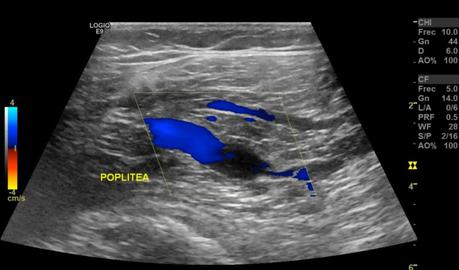

En el sistema venoso profundo, la valoración de las venas femoral común, femoral, femoral profunda, poplíteas, todas ellas presentaron flujo espontáneo y respiratorio fasico unidireccional con adecuada competencia valvular.